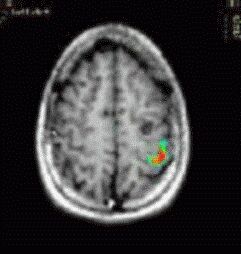

Caso 2

Paciente Paciente de sexo masculino de 13 años de edad.  Mapeo prequirúrgico de áreas elocuentes.

Paradigma Fluidez fonética

ACTIVADO: Generación en silencio de palabras que comienzan con una letra dada

DESACTIVADO: No pensar en nada

Resultados Fuerte activación en las circunvoluciones frontales inferiores y medias izquierdas, y el surco postcentral izquierdo.   No se observó ninguna activación significativa en el  hemisferio derecho.